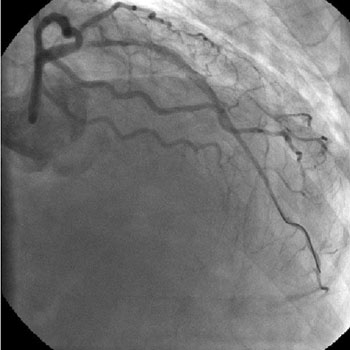

Angiography

1) RCA: Discrete severe mid stenosis (Figure 1)